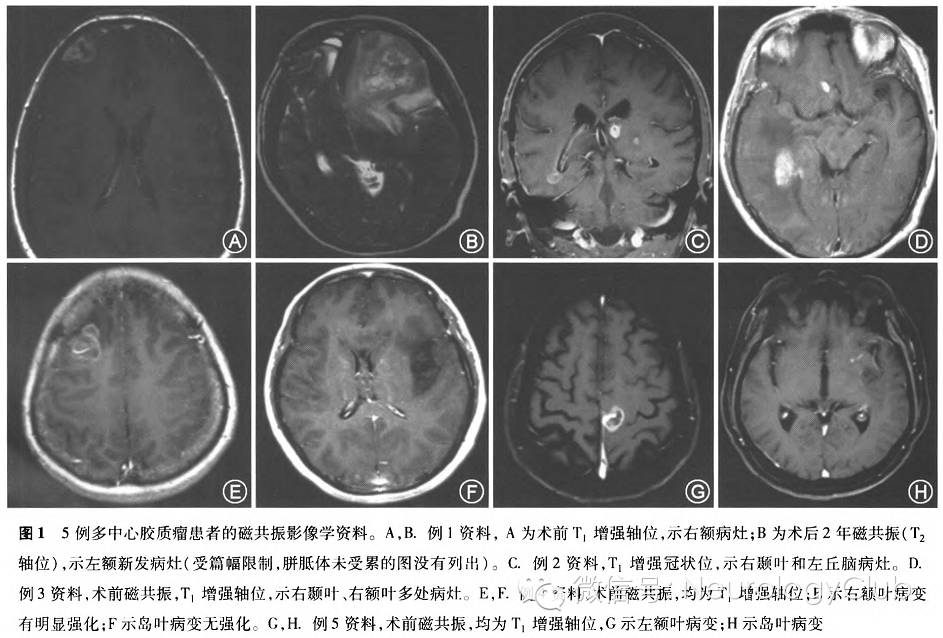

例1. 患者男,38岁,因发作性肢体抽搐1周入院。体格检查:无明显阳性体征。人院行头颅增强MRI示右侧额叶团块状长T1长T2异常信号,增强扫描呈明显不均匀环形强化(图1A),考虑为颅内肿瘤,行有额叶肿瘤全切除,术后病理学诊断:右额叶间变型星形胶质细胞瘤合并局灶胶质母细胞瘤(WHO IV)。术后予放疗及替莫唑胺同步及辅助化疗12个疗程。术后2年因头痛再次就诊,增强MRI见左额叶类圆形长T1长T2异常信号影,有明显不均匀强化,胼胝体无累及(图1B)。再次行左额叶肿瘤大部切除。术后病理学为胶质母细胞瘤(WHO IV级),术后予替莫唑胺节律方案(7d/7d)化疗+贝伐单抗靶向治疗,共4个疗程,但复查显示肿瘤仍持续进展,疾病进展后6个月时患者死亡,总体生存期30个月。

例2. 患者男,56岁,因右侧偏身感觉障碍伴右侧肢体乏力半年余入院。体格检查:右侧触觉、痛觉、温觉、本体感觉减退明显,右侧肢体肌力3级,右Babinski征阳性。MRI示左侧丘脑及右侧颞叶深部分别见团块状长T1长T2信号影,右颞叶病灶有强化,左侧丘脑病灶无强化(图1C)。入院前曾于外院接受针对左侧丘脑病变的三维适形分割放疗及替莫唑胺(TMZ 75mg/m^2)同步化疗,但右颞叶病变未行放射治疗。人院后行右颞叶肿瘤切除术,术中进行了肿瘤全切术。病理学为胶质母细胞瘤(WHO IV级),分子检测IDH1/2(-),MGMT启动子甲基化(-),1p19q杂合子突变(-)。术后患者接受针对右颞叶术区再次放疗和ACNU化疗。术后6个月复查MRI肿瘤进展,左侧丘脑和右侧脑室三角部出现多发增强灶,于术后8个月死亡,总体生存时间为14个月。

例3. 患者男,58岁,因头晕2年,加重伴头痛、恶心呕吐0.5个月人院。体格检查:理解力轻度下降,四肢肌力、肌张力正常,病理症阴性。MRI见右侧脑室三角部脑室旁和右额叶片状水肿,中线移位,增强见右颞叶片状不规则增强影(大小5.4cm×3.4cm×3.8cm)、右侧额叶增强后见多个强化结节影(图1D)。行右颞叶肿瘤切除近全切除,术后病理学为胶质母细胞瘤(WHO IV级),术后患者症状短期改善,随后加重并出现意识障碍,1个月时复查即见术区肿瘤复发,而且右额多发病灶也进一步进展。行多发病灶的放疗和替莫唑胺同步化疗,同时给予贝伐单抗治疗脑水肿,患者意识逐渐清醒,症状显著好转,术后6个月随访患者仍然生存,KPS评分90分。

例4. 患者女,46岁,因头晕头胀2.5个月,加重20d入院。体格检查:无阳性体征。MRI示右侧额叶团块状及左侧额岛叶大片状长T1长T2信号影,其中右侧额叶病变见环形强化(图1E,F),考虑为颅内肿瘤,行右额叶肿瘤全切除,病理学诊断为胶质母细胞瘤(WHO IV级)。术后患者拒绝对侧病变切除和进一步治疗,术后6个月肿瘤进展,术后7个月患者死亡。

例5. 患者男,70岁,因右下肢乏力4个月、抽搐2个月人院,既往有膀胱癌手术史5年。体格检查:右下肢肌力4级,躯体感觉正常,病理征阴性。MRI示左顶叶见长径约3.0cm混杂信号影,周围水肿带,病灶呈环形强化,左侧基底节区、颞叶见斑片状长T1长T2信号影,未见明显强化(图1G,H)。行左顶叶中央区脑瘤全切除,术后病理学诊断为胶质母细胞瘤(WHO IV级),术后接受替莫唑胺化疗1次。术后2个月复查头颅增强MRI提示左侧基底节区、颞叶病变快速进展,出现中线附近的多个散在的增强灶,遂放弃行对侧病变的手术治疗,行放疗和替莫唑胺同步化疗,术后4个月随访患者仍然生存,KPS评分80分。